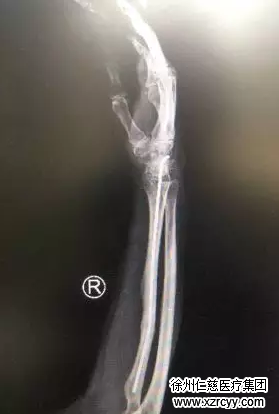

前臂钢针取出后X线片